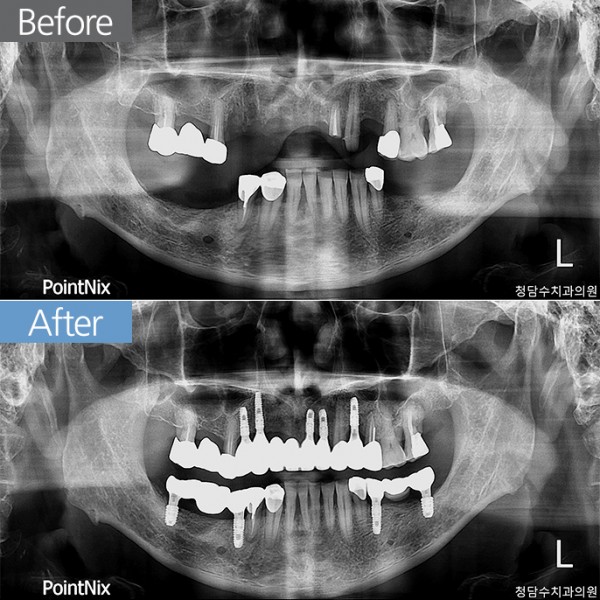

임플란트 70대남 임플란트

70대남 임플란트